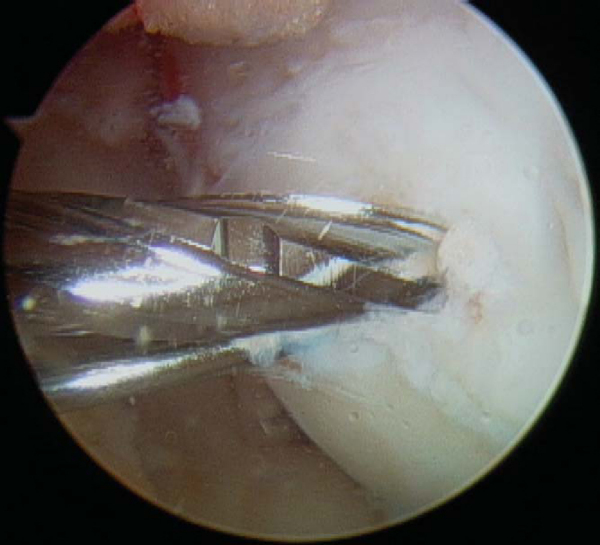

With use of the elbow of a standard arthroscopic probe, the boundaries and stability of the lesion are assessed. In many cases, the borders of the lesion are obvious, with fissuring, fibrillation, and even gross gapping in the articular surface (

Fig. 53-3

). However, definition of the lesion can be more subtle in some cases. Nevertheless, even without obvious visual clues, a distinct transition from firm to soft or the ballottement of a segment of articular cartilage can typically be appreciated as one moves the elbow of the probe from normal cartilage to that overlying an osteochondritis dissecans lesion. The tactile feedback received is that of the elbow of the probe falling into a small crevasse as the lesion boundary is crossed (

Fig. 53-4

). In the rare case that the lesion cannot be identified through visualization and tactile feedback, intraoperative fluoroscopy can confirm the lesion’s location.